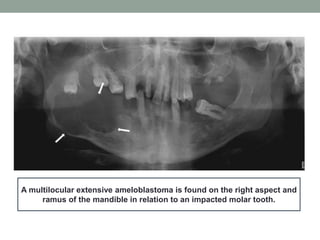

A multilocular extensive ameloblastoma is found on the right aspect and

ramus of the mandible in relation to an impacted molar tooth.

A multilocular extensiveameloblastoma is found on the right aspect and ramus of the mandible in relation to an impacted molar tooth.